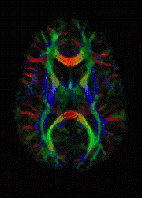

تصویرگیری تنسور پخش

تصویرگیری تنسور پخش (به انگلیسی: Diffusion Tensor Imaging) یا به اختصار DTI، نوعی روش تصویرگیری در ام آر آی است.

در این روش، آناتومی رشتههای ماده سفید مغزی را میتوان بوسیله گرادیانهای میدان مغناطیسی متفاوتی از روش تصویربرداری پخش وزنی نقشه برداری کرد.[1]

از این روش زمانی استفاده میکنیم که تنسور پخش بافتها حالتی ناهمسانگرد داشته باشد.